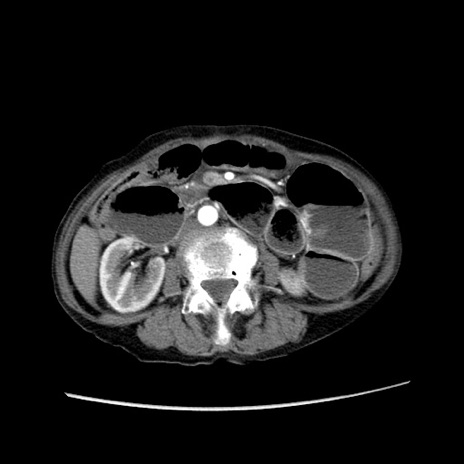

冠状断像

【症例】80歳代女性

【主訴】胸のつかえ感

【現病歴】約9時間前に食後から胸のつかえた感じあり、嘔吐あり、来院。

【既往歴】胃癌(全摘)、胆摘、虫垂炎

【身体所見】心窩部に圧痛あり、反跳痛なし。

【データ】WBC 5700、CRP 0.05